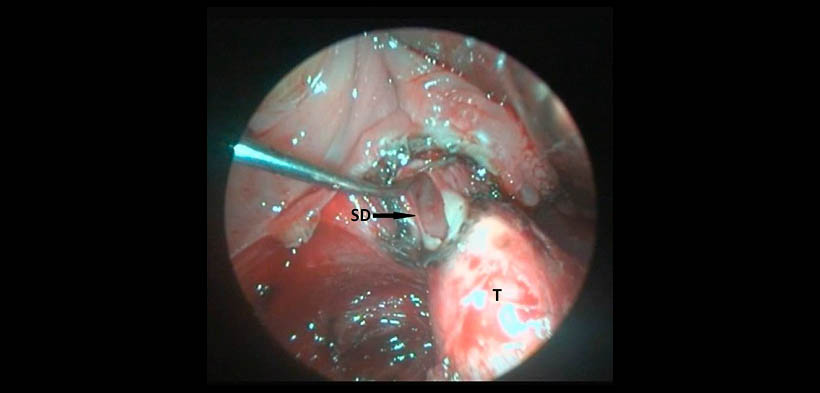

Fig. 2. Imagen intraoral intraoperatoria que muestra la abertura del conducto salival accesorio (SD) de la glándula submandibular izquierda a nivel del polo inferior de la amígdala, (T) tonilolito.